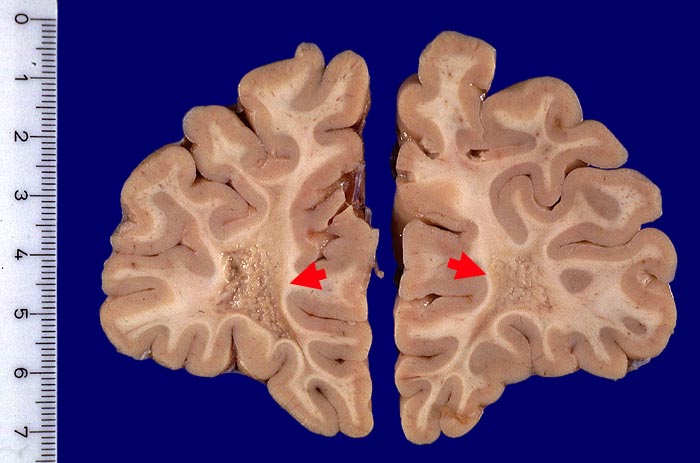

Alte Entmarkungsherde frontoorbital beidseits

Grau verfärbte und eingesunkene Areale mit granulärer Oberfläche im frontalen Marklager beidseits.

Alte Entmarkungsherde (Dm 1,5cm) der frontoorbitalen Marksubstanz links und des Balkenknies (Dm 0,5cm): teilweise wiederbemarkte nicht aktive Multiple Sklerose Herde

Keine Symptomatik bekannt. Sogenannte silent multiple sclerosis.